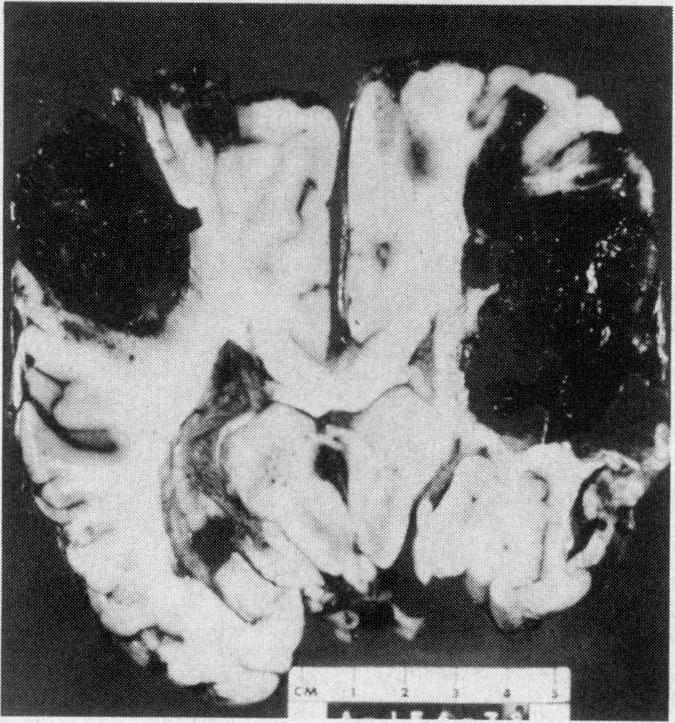

Four days after the onset of a severe headache a 22-year-old woman who had been taking oral contraceptives for less than three weeks had a convulsion, followed by right hemiparesis. Other focal neurologic signs and evidence of raised intracranial pressure appeared, and she became comatose on the seventh day. A left craniotomy revealed extensive cerebral venous thrombosis. She died the next day. On postmortem examination extensive thrombosis of the superior sagittal sinus and draining cerebral veins, and multiple areas of cerebral hemorrhage and hemorrhagic infarction were seen. Some of the superficial cerebral veins showed focal necrosis of their walls, and the lateral lacunae of the superior sagittal sinus contained proliferating endothelial cells. The adrenal veins were also thrombosed. The significance of these findings is discussed. The literature on cerebrovascular complications of oral contraception, particularly cerebral venous thrombosis, is reviewed.

一名22岁女性,服用口服避孕药不到三周,在严重头痛发作四天后出现惊厥,随后出现右侧偏瘫。其他局灶性神经体征及颅内压升高的证据出现,她在第七天昏迷。左侧开颅手术显示广泛的脑静脉血栓形成。她于次日死亡。尸检发现上矢状窦及引流脑静脉广泛血栓形成,并有多处脑出血和出血性梗死。一些脑浅表静脉显示管壁局灶性坏死,上矢状窦外侧陷窝内可见内皮细胞增生。肾上腺静脉也有血栓形成。讨论了这些发现的意义。综述了口服避孕药脑血管并发症的文献,特别是脑静脉血栓形成方面的文献。